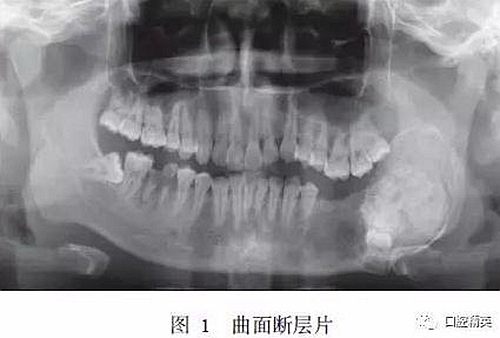

入院時??撇轶w:患者面型不對稱,開口度正常,開口型偏左側(cè)。左下頜膨隆明顯,范圍約5.0 cm×3.0 cm,向前延伸至D5根尖處,向后延伸至下頜升支,質(zhì)硬,觸之無乒乓樣感。口內(nèi)檢查示D5~D8缺失,左側(cè)頜下有一腫大淋巴結(jié),質(zhì)硬,活動,大小約1.5 cm×1.5 cm。曲面斷層片示:左下頜D4根尖區(qū)至左下頜升支乙狀切跡下方可見一異常高密度團(tuán)塊影,團(tuán)塊中心密度不均勻,病變邊緣光滑,周緣可見低密度條帶影包繞,D5~D8牙埋伏阻生于病變內(nèi),似不規(guī)則小牙體征象,病變區(qū)頜骨向頰舌向膨隆明顯,下頜神經(jīng)管受壓后向下移位(圖1)。

錐形束CT示:左下頜D5~D7缺失,D5~D7位置下頜骨內(nèi)可見牙瘤樣結(jié)構(gòu),左下頜骨膨隆明顯,膨隆向上至下頜骨升支乙狀切跡下方,向下至下頜骨下緣,向前至下頜骨體D5位置,向后至下頜升支中份,骨質(zhì)膨隆內(nèi)可見鈣化程度不同的阻射影(圖2)。